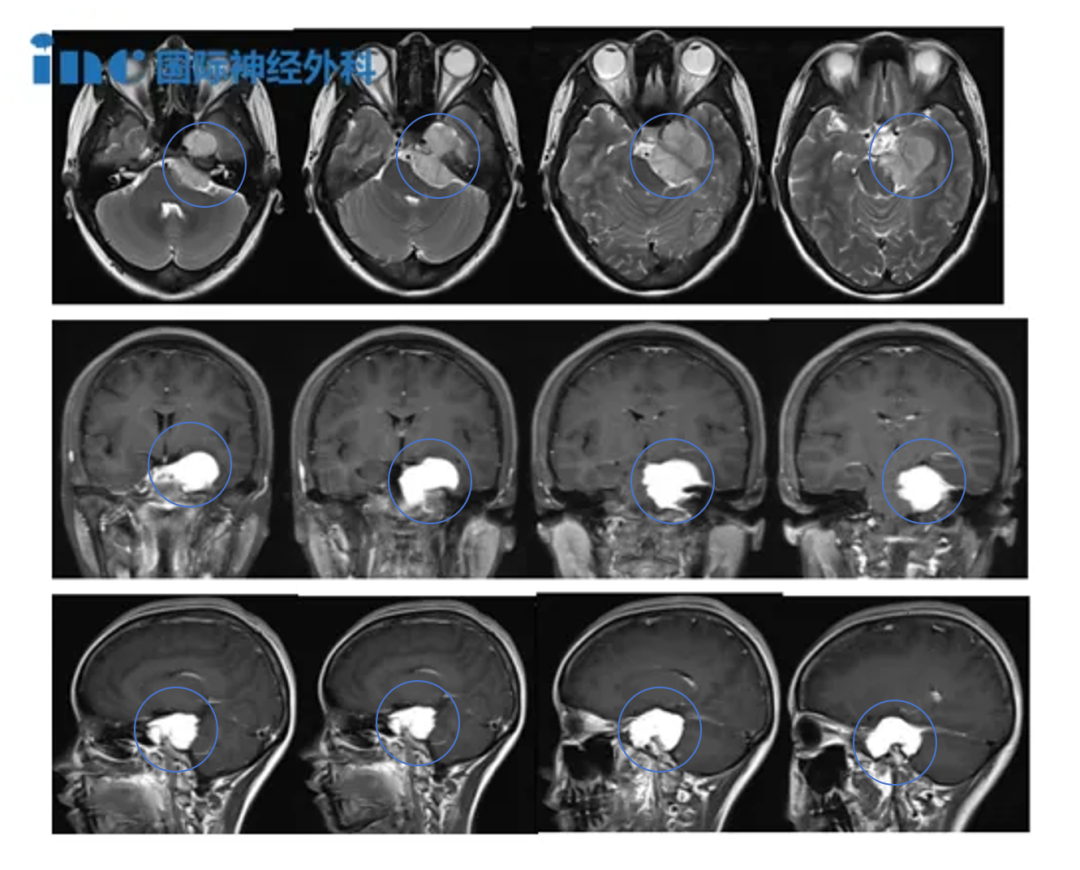

患者为75岁男性,因进行性头痛及共济失调症状持续数周前往某医院就诊,期间多次出现跌倒现象。症状评估期间的头颅MRI检查显示,起源于上斜坡区域的4.2×3.4厘米脑膜瘤。肿瘤占据桥前池大部分空间,向上延伸至交叉池水平,向下抵达内听道,向外侧侵入右侧中颅窝。基底动脉被肿瘤完全包裹,脑桥及脑干呈现显著占位效应与水肿表现。

遗憾的是,患者术后持续处于昏迷状态。术后MRI检查显示脑桥内存在大面积梗死灶。经过数周观察神经功能无改善,并经与家属、神经外科团队及姑息治疗团队深入讨论后,家属选择转为舒缓治疗,患者最终离世。